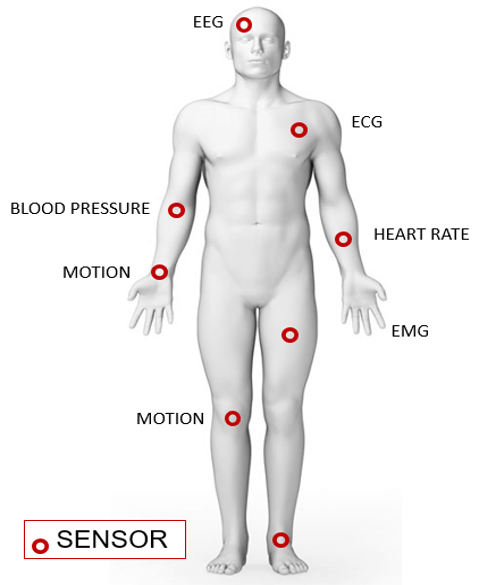

Wireless Body Area Network (WBAN)

Wireless Body Area Network (WBAN) is a technique used for remotely monitoring the patient’s health and gathering the related information from the embodied sensors. It consists of a small wireless network that contains several small devices, i.e. sensor nodes and actuators. The sensor nodes are placed directly either on the body or under the skin of a person to compute certain body parameters such as an electrocardiogram (ECG), electroencephalogram (EEG), body movement, temperature, blood pressure, blood glucose, and respirations.